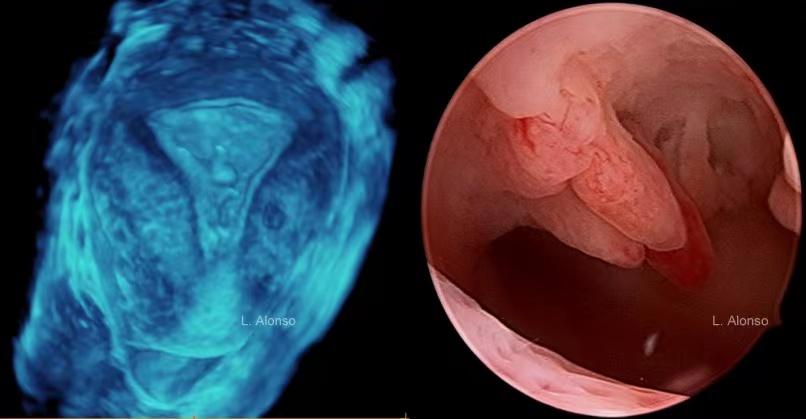

如何诊断子宫内膜息肉?

超声诊断是目前最常用的初步诊断子宫内膜息肉的检查方法。一般建议在月经干净3天左右(三线征时)做超声,此时内膜较薄,避免了分泌期内膜息肉样形态与之混淆。

超声图像可见:

1、宫腔内不均匀中强回声团,可呈梭形或者水滴形,单个或者多个;

2、息肉较大时可充满整个宫腔,多发生囊变,息肉边缘与正常内膜间界限清晰可辨(双边征),内膜线可移位;

3、小的子宫内膜息肉可无明显的血流信号,较大者息肉根蒂部可见点状或者条状血流信号。